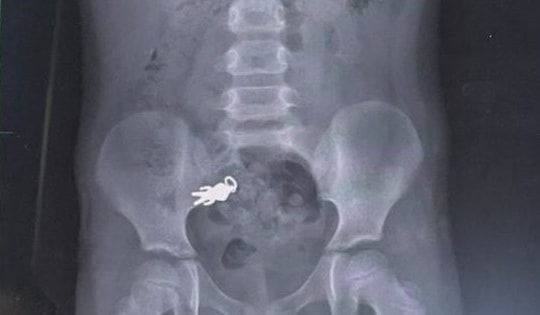

Chụp X-quang bụng bé trai 7 tuổi, bác sĩ sốc nặng khi phát hiện thứ bên trong

Ngay sau khi phát hiện bé trai 7 tuổi nuốt phải dị vật, gia đình đã đưa cậu bé đến bệnh viện kiểm tra.